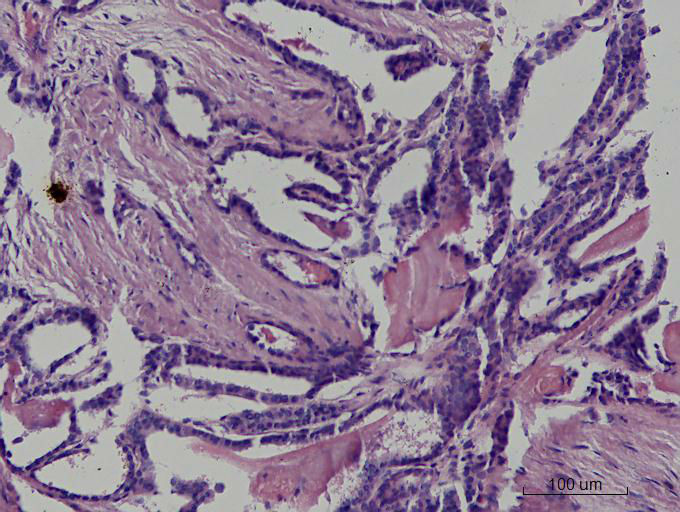

女43岁,甲状腺肿物

呵呵,大家看看够不够乳头状癌?图12-15再清晰些会更好。

嗯。图不好,不敢妄谈。但乳头相对比较宽大,细胞核大多圆形,可以排除经典型(common type)。

乳头状癌

就目前的切片看本例没有形成明确的以纤维结缔组织为轴心的乳头结构,前15张图更是连乳头状癌特有的核的表现(核拥挤、核沟、核内假包含体、毛玻璃核等)也不明显,而后传的7张图中核的改变都比前15张图中要明显,个人绝得诊断乳头状癌缺乏重要依据(1)明确的乳头结构(2)核拥挤、核沟、核内假包含体、毛玻璃核,所以希望重取材,多切片搜索可靠的诊断依据再下结论。

通过所给图片具备了乳头状结构,也有了核的一些特征,虽不典型:1、核椭圆形,2、核拥挤重叠,3、核上下分层,4、核沟等,可以诊断乳头状癌。